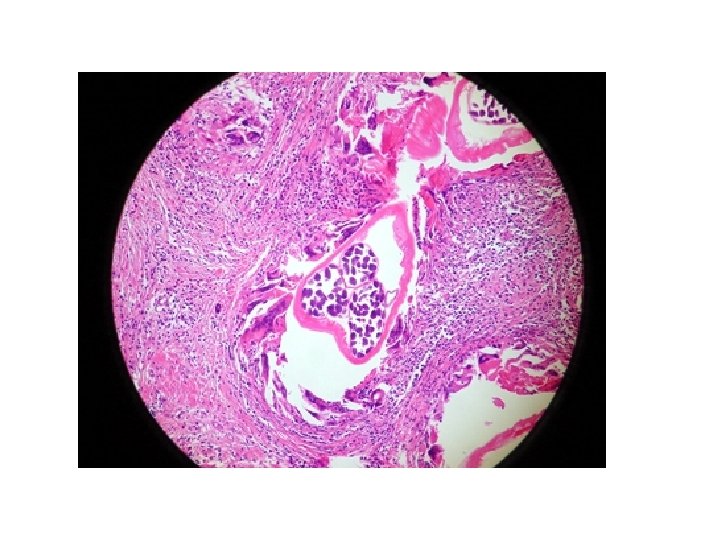

Onchcerca volvulus -Skin Nodule Section with adult female and microfilariae In the surrounding fibrous connective tissues